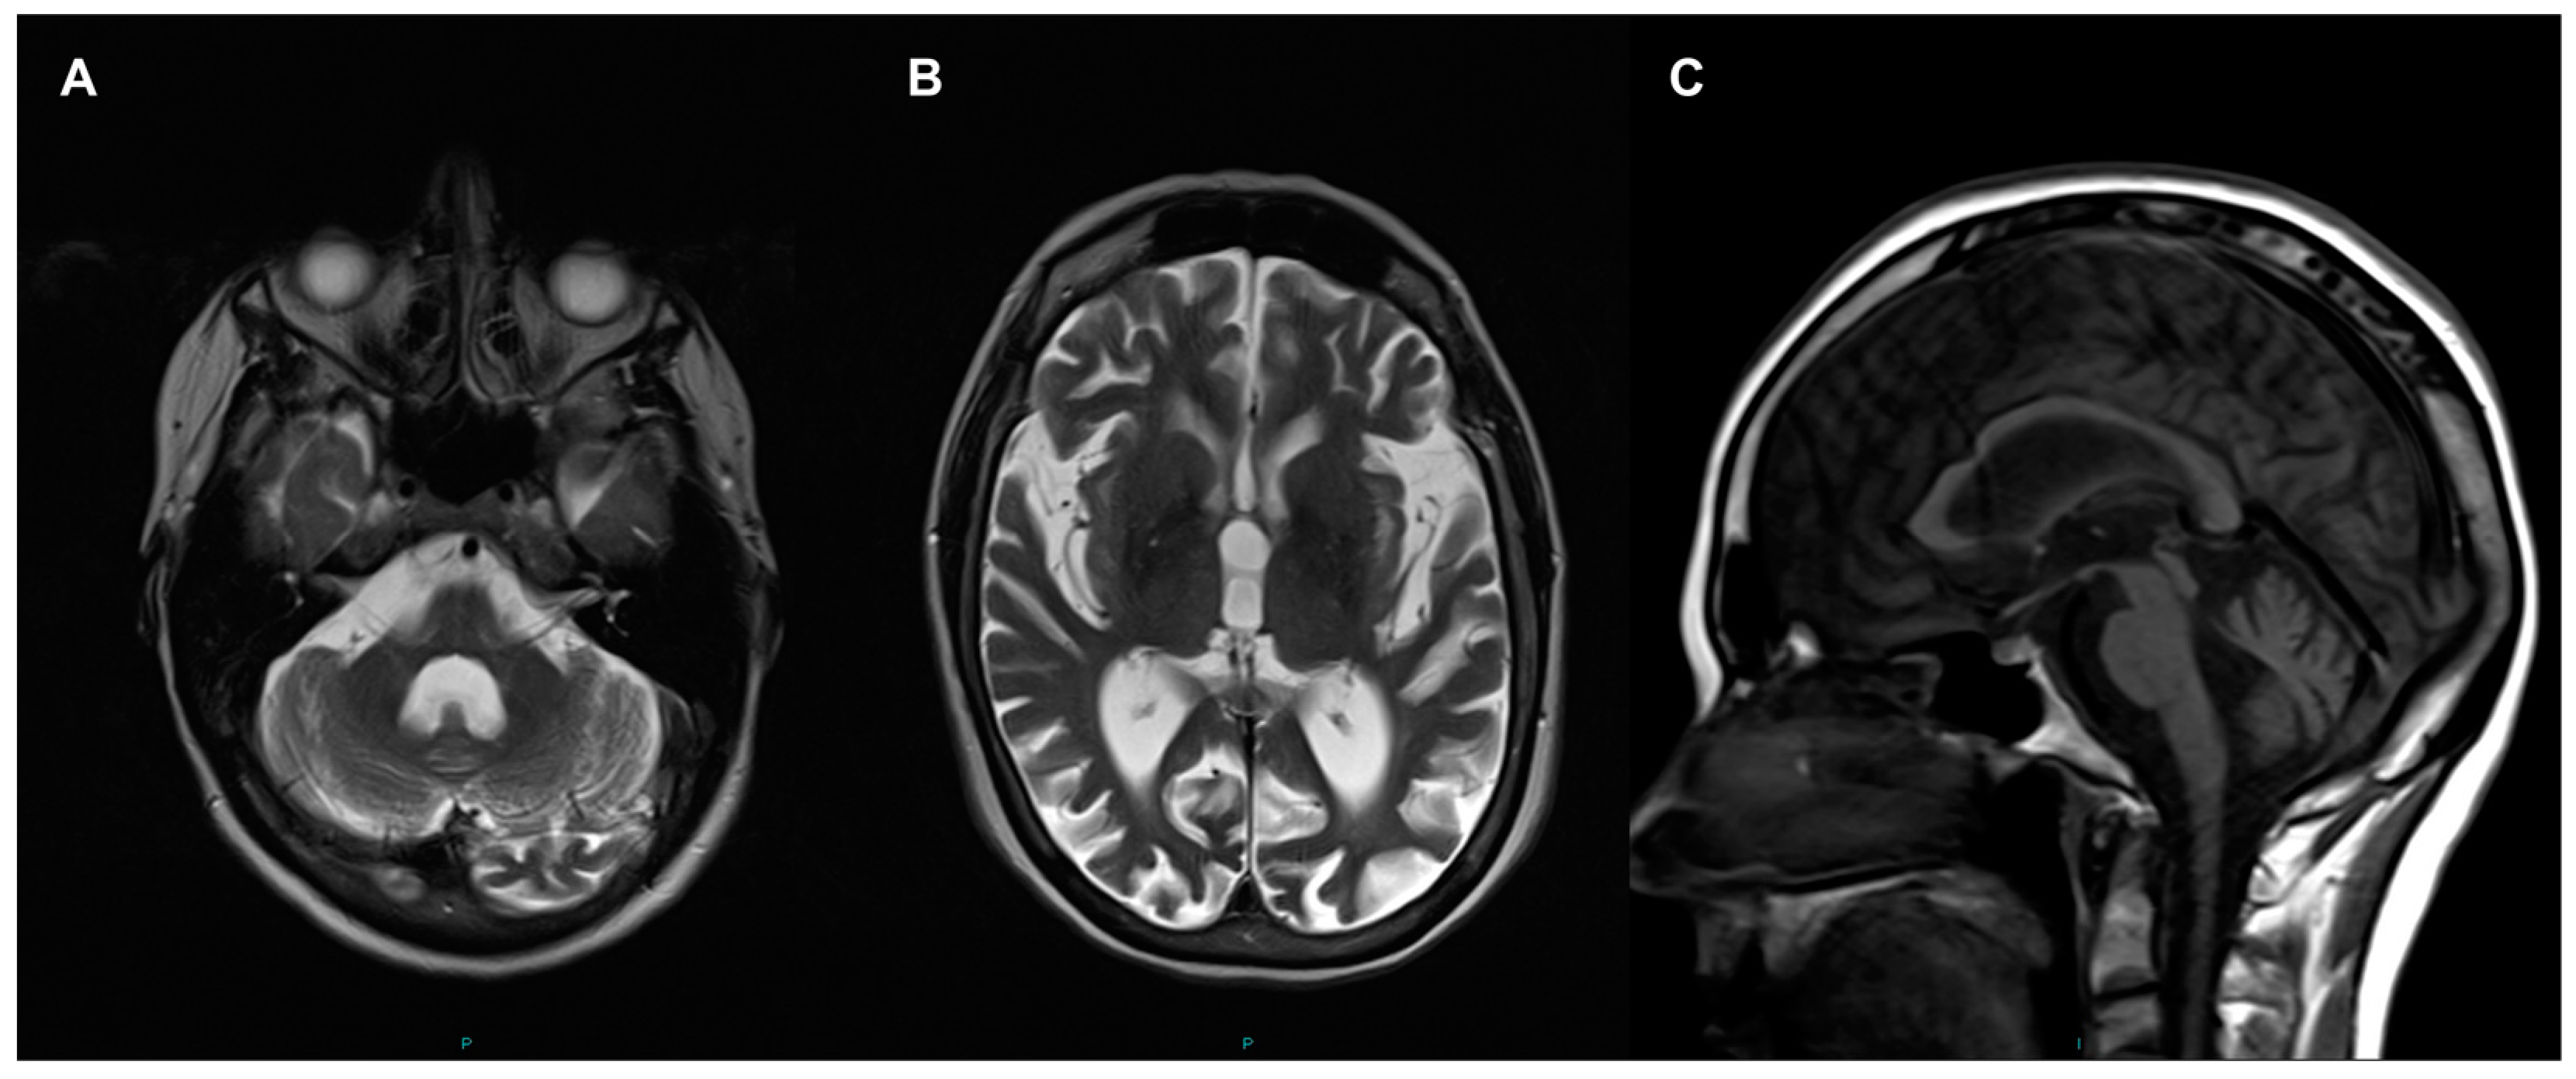

Routine laboratory investigations including blood count, kidney and liver functions, HbA1c, creatinine kinase level and resting serum lactate were normal except borderline primary hyperthyroidism was identified (TSH 0.26, range 0.3–4.7 mU/L; free thyroxine 23.4, range 9.5–21.5 pmol/L; free T3 5.7, range 3.5–6.5 pmol/L). Her resting 12-lead electrocardiogram and echocardiography were normal. Cranial magnetic resonance imaging (MRI)showed severe cerebral (particularly affecting occipital, parietal and frontal lobes) and cerebellar atrophy (Figure 1); there was no signal abnormality in the basal ganglia. There was some confluent periventricular T2 signal symmetrical change. Nerve conduction studies and electromyography (EMG) identified changes that were consistent with a moderate large fiber axonal sensorimotor neuropathy with features suggesting a length-dependent distribution. However, there was no evidence of myopathy.

Figure 1.

Cranial magnetic resonance imaging (MRI) performed at age 46 years. Enlarged 4th ventricle and hemispheric atrophy of cerebellum (A); and dilated ventricles and generalised cerebral atrophy shown in axial T2 (B); Sagittal T1 view shows cerebellar atrophy and normal brainstem (C).